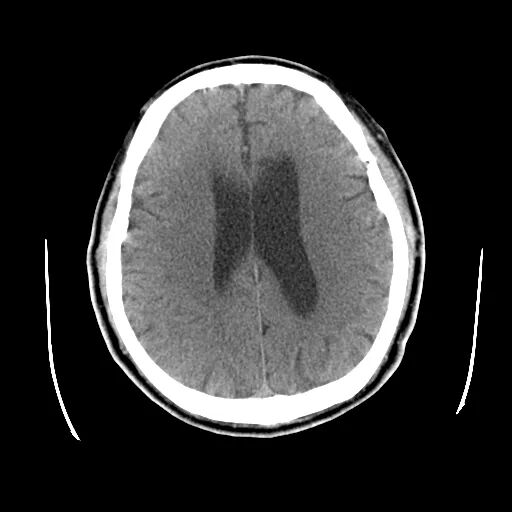

术前影像

颅脑CT:颅内多发腔隙性梗塞灶。

颅脑磁共振+头颈MRA:未见新发梗死;右侧颈内动脉C1段重度狭窄。